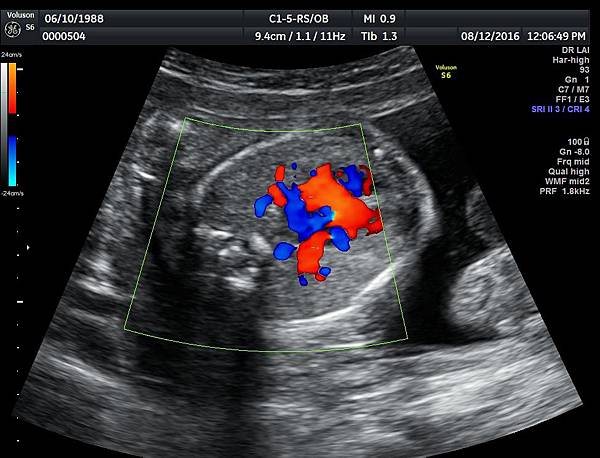

我看肺靜脈的心路歷程可以分成三個階段,第一個階段是用gray scale(黑白)看到左右肺靜脈下行支回到左心房(附圖 1.2.),第二個階段是用flow(彩色)看到左右肺靜脈回到左心房(附圖 3.4.),第三階段是同時要看到黑白和彩色的左右肺靜脈回到左心房,為什麼只有看flow(彩色)不安全呢?因為右肺靜脈的flow有時候是假影,為何會看到假影?因為右心房到左心房的flow overlapping(重疊)造成的(附圖 5.),如何判斷是假影,只要關掉flow看黑白的即可證明右肺靜脈沒有進入左心房(附圖 6.)。

如果同時看到左右肺靜脈進入左心房,這種誤判的機率下降很多,如果只能看到一條肺靜脈的血流,我會選擇左肺靜脈(附圖 7.8.),因為左肺靜脈的血流比較不會被overlapping,最安全的方法是黑白和彩色都看到左右肺靜脈進入左心房,只是需要胎兒姿勢配合,當然孕婦的體重也是需要考量的因素。